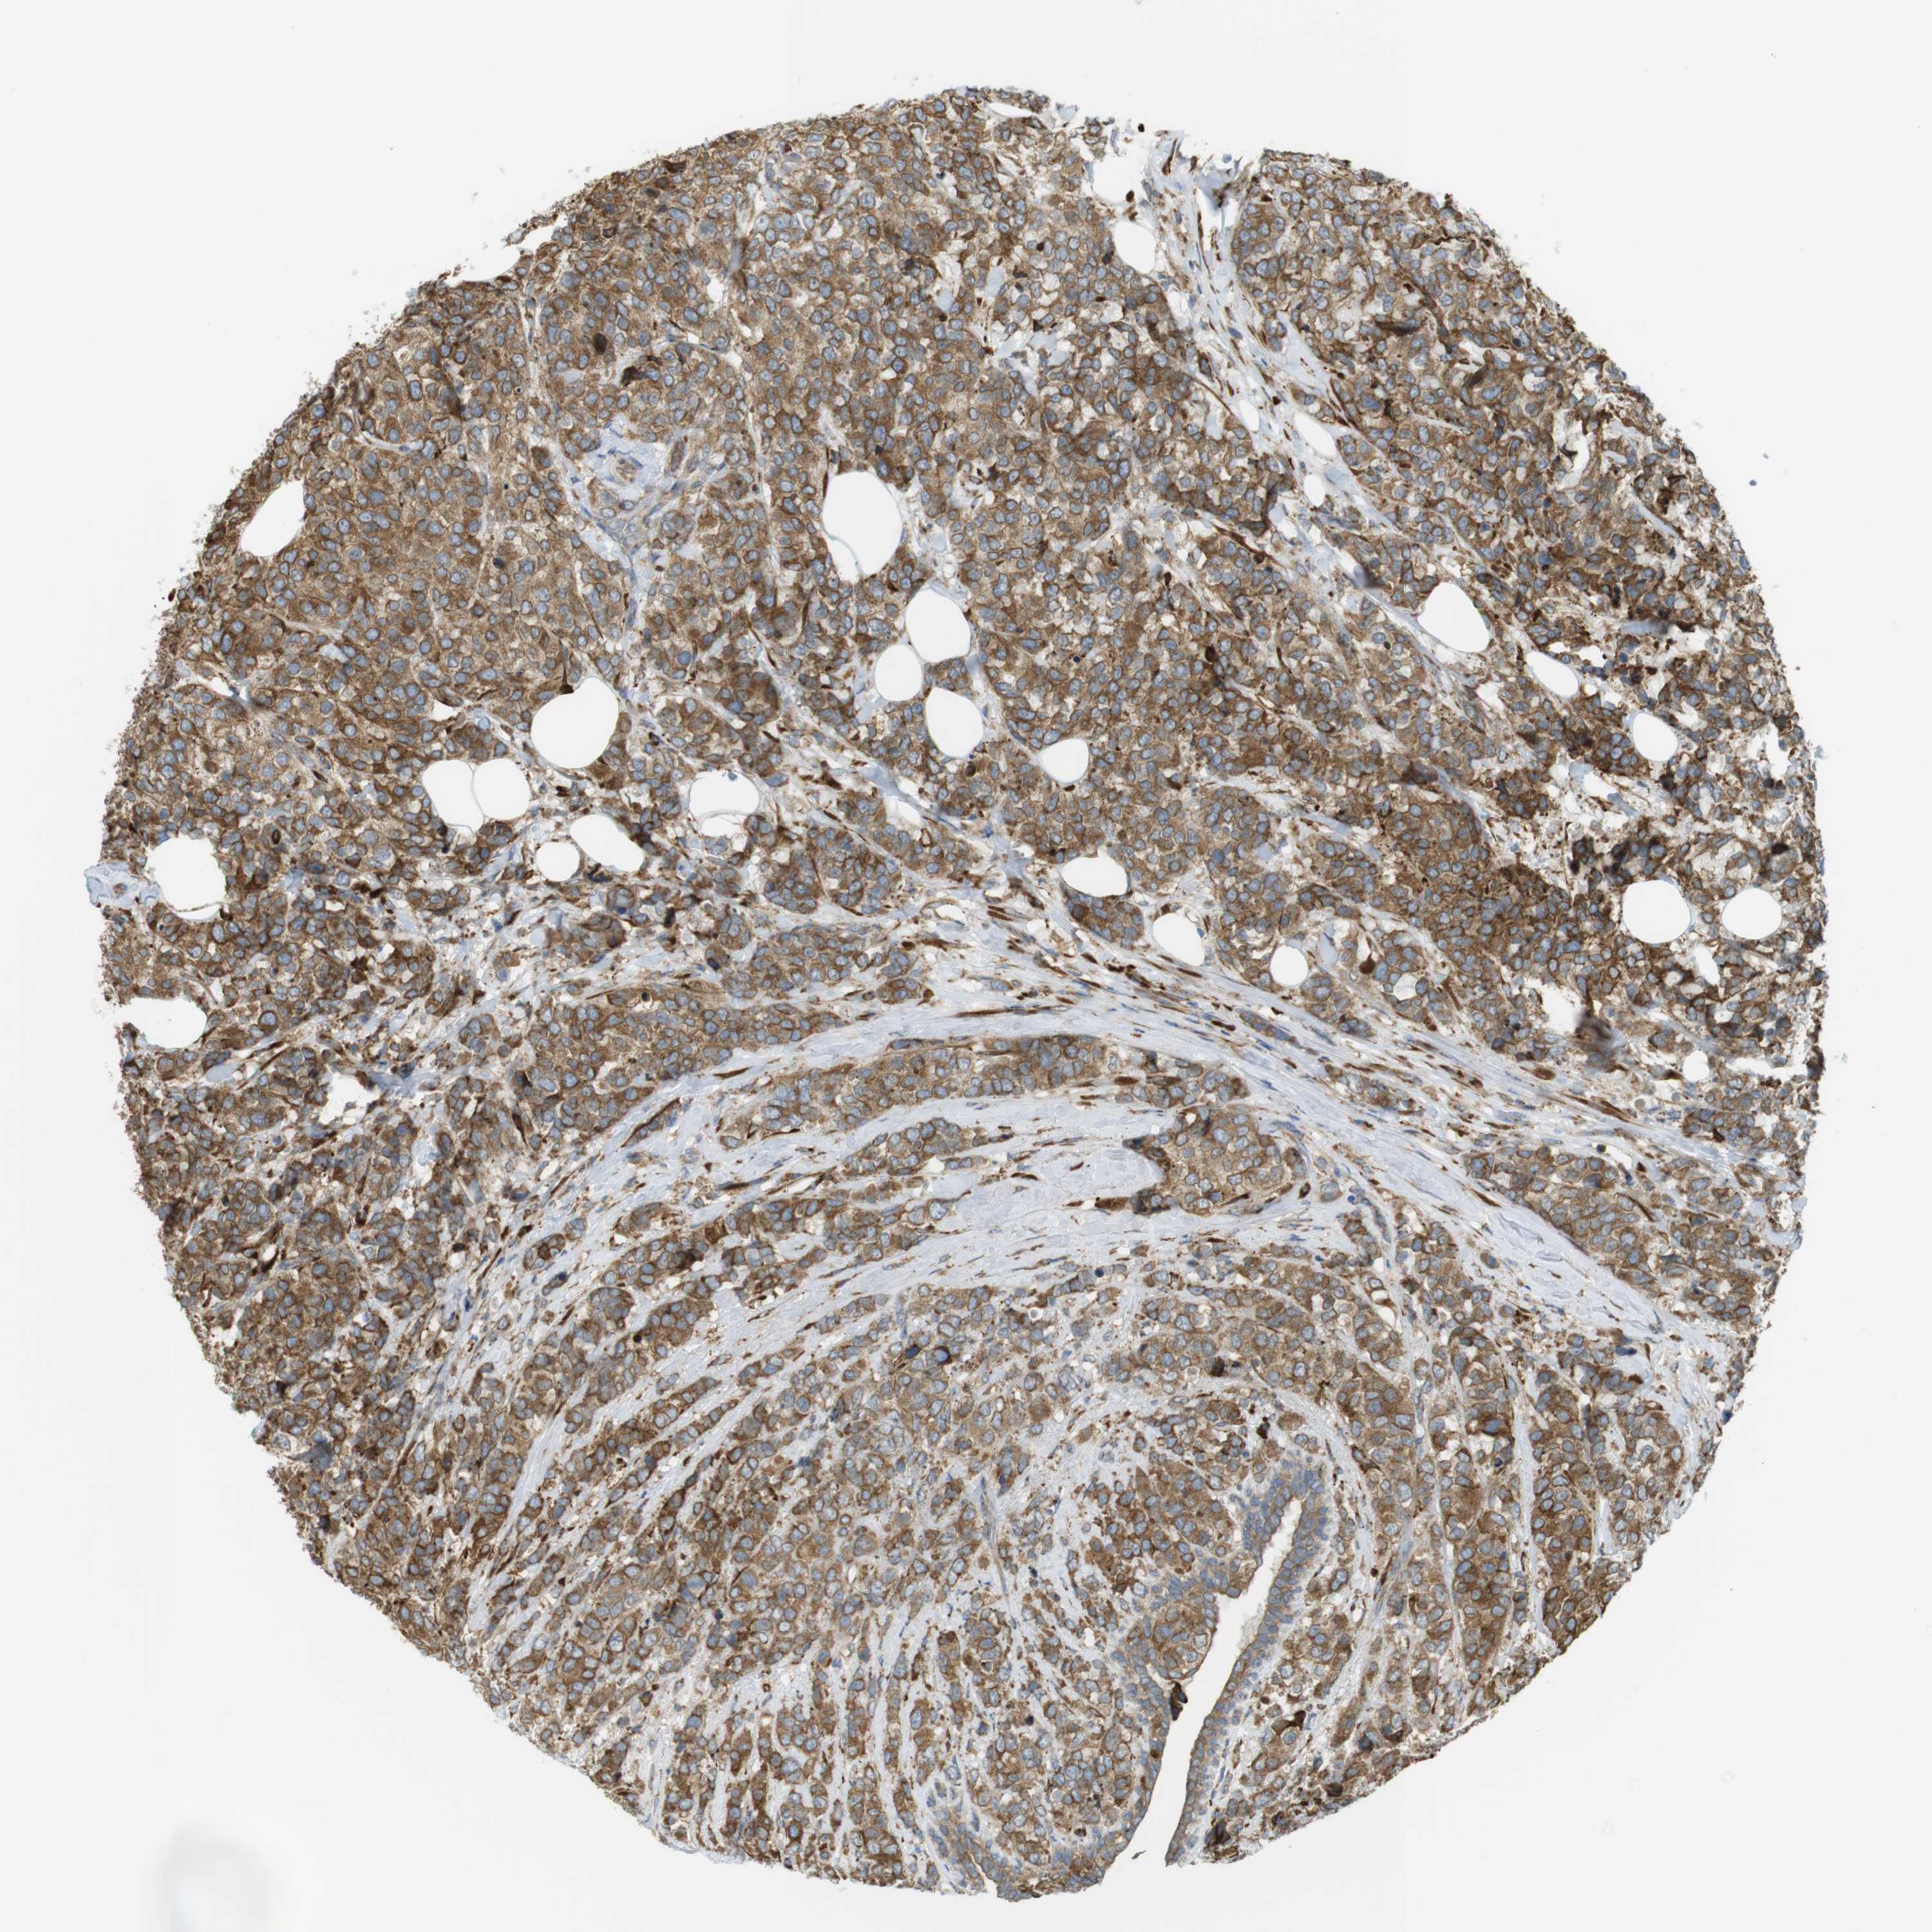

BRCA TCGA BRCA VALIDATION PROTEIN EXPRESSION

ANTIBODIES

AND

VALIDATION